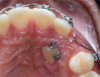

• Pose de l'appareil multi-attaches et activations de celui-ci jusqu'à retrouver la place suffisante pour la dent incluse

• Sous anesthésie : dégagement chirurgical de la gencive et de l’os qui recouvre la canine

• collage d’une attache sur la canine afin de permettre sa traction dans l’axe souhaité

• Mise en place d’un système de traction (barre transpalatine par exemple si canine maxillaire incluse en position palatine) pour la diriger vers sa position physiologique

• Quand la canine est assez descendue, suppression du dispositif de traction et suite du déplacement grâce à l'appareil multi-attaches.

EXEMPLE DE CAS TRAITE AU CABINET (CORALIE) : AVANT/APRES